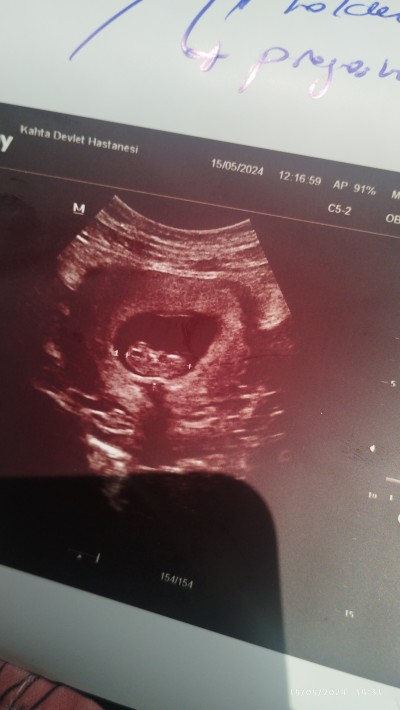

9+5 cinsiyet tahmininde bulunabilirmisiniz

Kız canm Allah bilir en iyisini